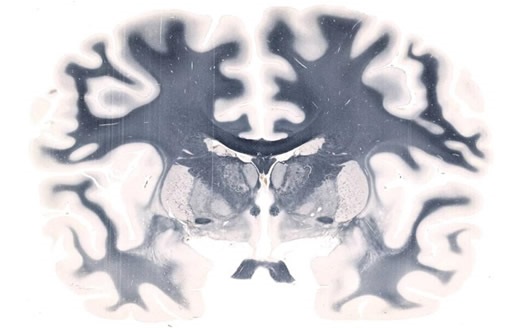

Whole-mount Brain scanned on a 5" x 7" slide at 20X resolution

Figure 1. Whole-mount Brain scanned on a 5" x 7" slide at 20X resolution. Image credit: Huron Digital Pathology.

Whole-mount slide imaging enables innovative processes and outcomes in brain research. Since the TissueScope can accommodate slides of up to 6 x 8”, it is possible to scan an entire slice of the brain at once, allowing a precise 3D reconstruction of the whole brain to be created. In contrast to conventional microscopy, sections need not be excluded, meaning a global image is easier to obtain. To reconstruct a brain image from histology slides, the brain needs to be thinly sliced along one axis. Although thousands of slides require scanning, the TissueScope can image whole slides in just a few minutes. Furthermore, accessories such as the TissueSnap™ enhance throughput by offloading preview scanning and pre-processing, meaning the main scanner can operate at maximum speed and without interruption.

It is possible to use a tiling algorithm, so that for each brain slice, thousands of evenly spaced scans are captured at high resolution. The resolution achieved using the TissueScope, can reach up to 0.25μm at 40x magnification or resolution can be lower, at 0.50μm at 20x, or 1μm at 10x. This enables researchers to map the brain in detail, at a cellular level, and the potential to clarify uncertainties over observations made with lower resolution in-vivo imaging. Using suitable software, brain slice images can be compiled into a 3D volume. Hundreds of sections can be processed and viewed in just a few minutes, owing to the 3D histology software Huron offers that provides volumetric reconstruction of whole-mount slides. Furthermore, volumetric images from optical and confocal z-stacks can be read, visualized and investigated. Form there, scientists can proceed with cell counting, measuring the volume of specific regions and much more.